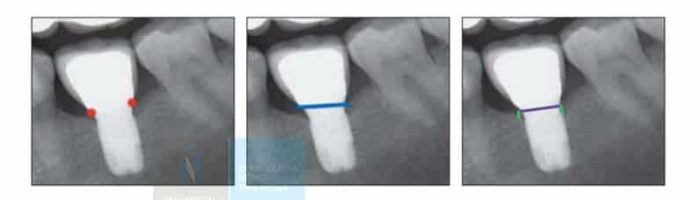

También se considera una cirugía bucal la cirugía periapical. Esta cirugía se realiza en casos de fracaso de una endodoncia. Antes de extraer un diente endodonciado que vuelve a presentar infección en muchas ocasiones puede realizarse una cirugía periapical para acceder a eliminar directamente la infección, y dar una nueva oportunidad a este diente.